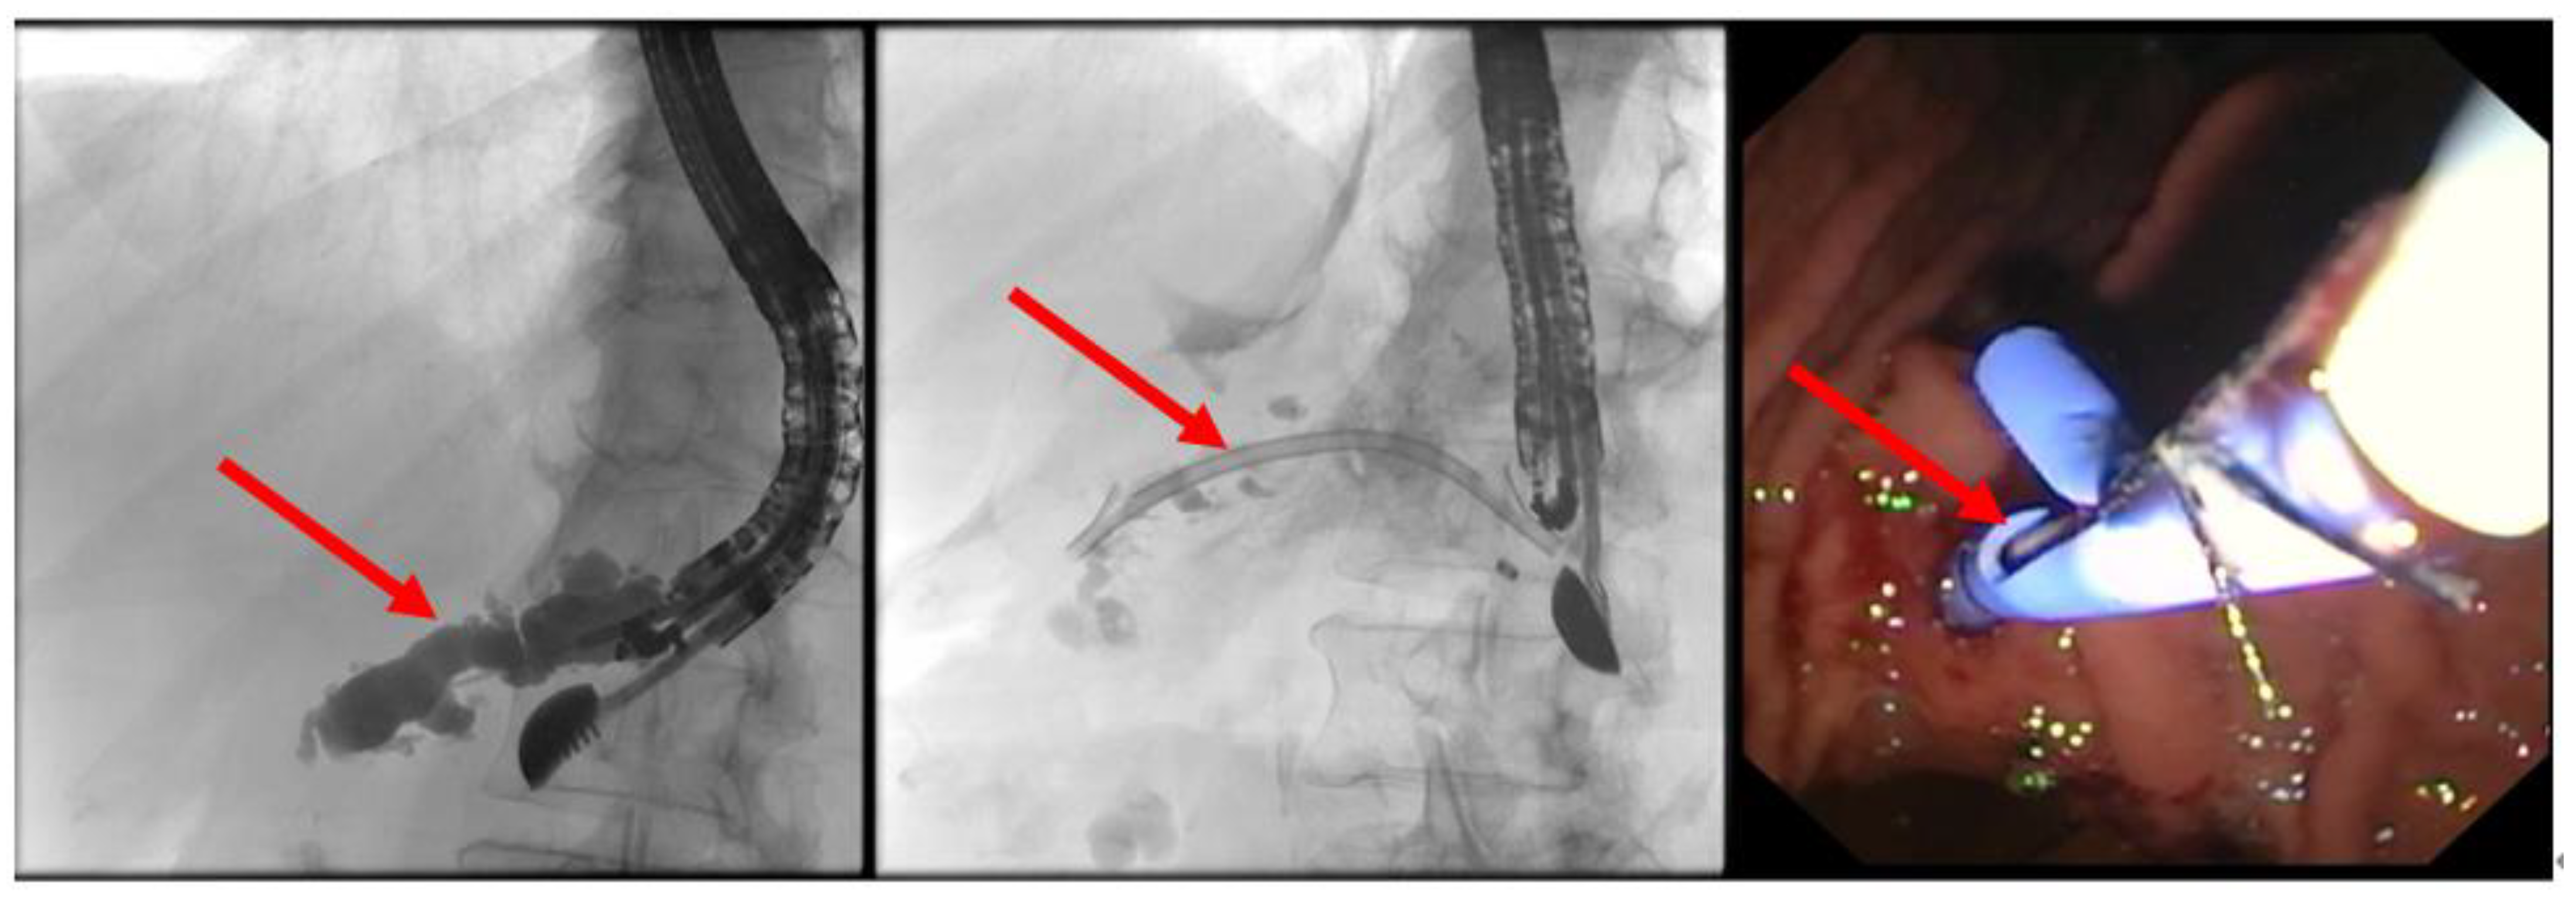

In cases where the puncture is distant from the obstruction (such as in the pancreatic body or tail), retrograde drainage into the stomach (pancreaticogastrostomy) is pursued. This procedure also utilizes metal stents or straight plastic stents (Figure 6 and Figure 7).

The advantage of using a metal stent (such as Hanaro® by Olympus, Hamburg, Germany, or SEM by Boston, Ratingen, Germany) lies in the possibility of later transmural targeted intervention in the pancreatic duct with a pancreaticoscope (such as SpyGlass by Boston Scientific, Ratingen, Germany). This option should be considered if primarily impassable strictures or obstructing pancreaticoliths are suspected, as these can be treated via targeted visual inspection. Pancreaticoliths, for example, can be fragmented and removed using pancreaticoscopic electrohydraulic lithotripsy (EHL), thereby restoring physiological antegrade drainage (Figure 8).

Figure 8. Following the retrograde placement of a self-expanding metal stent (red arrow)—left panel, the obstructing pancreaticolith is destroyed with an EHL probe (red arrow; middle panel), restoring the pathway through the papilla (red arrow; fluoroscopy control—right panel), selected from the clinical picture library of the reporting Dept. of Gastroenterology, Hepatology and General Internal Medicine.